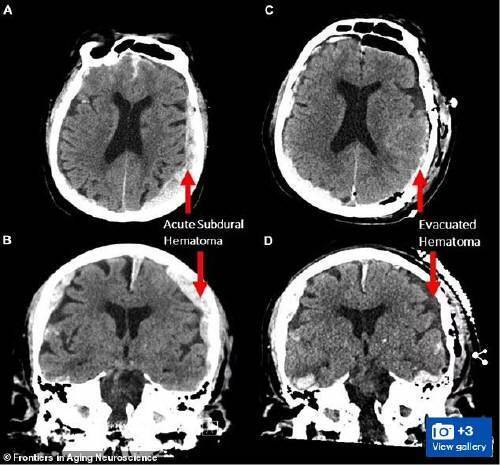

뇌전증(간질)이 발생한 해당 환자(87세)는 뇌파를 측정하던 도중 갑작스럽게 심장마비로 사망했다.

다만 해당 환자는 뇌전증이었고, 출혈이 있고, 뇌가 부어 있었기 때문에 하나의 연구만으로 광범위한 결론을 도출할 수는 없다고 연구팀은 부연했다.